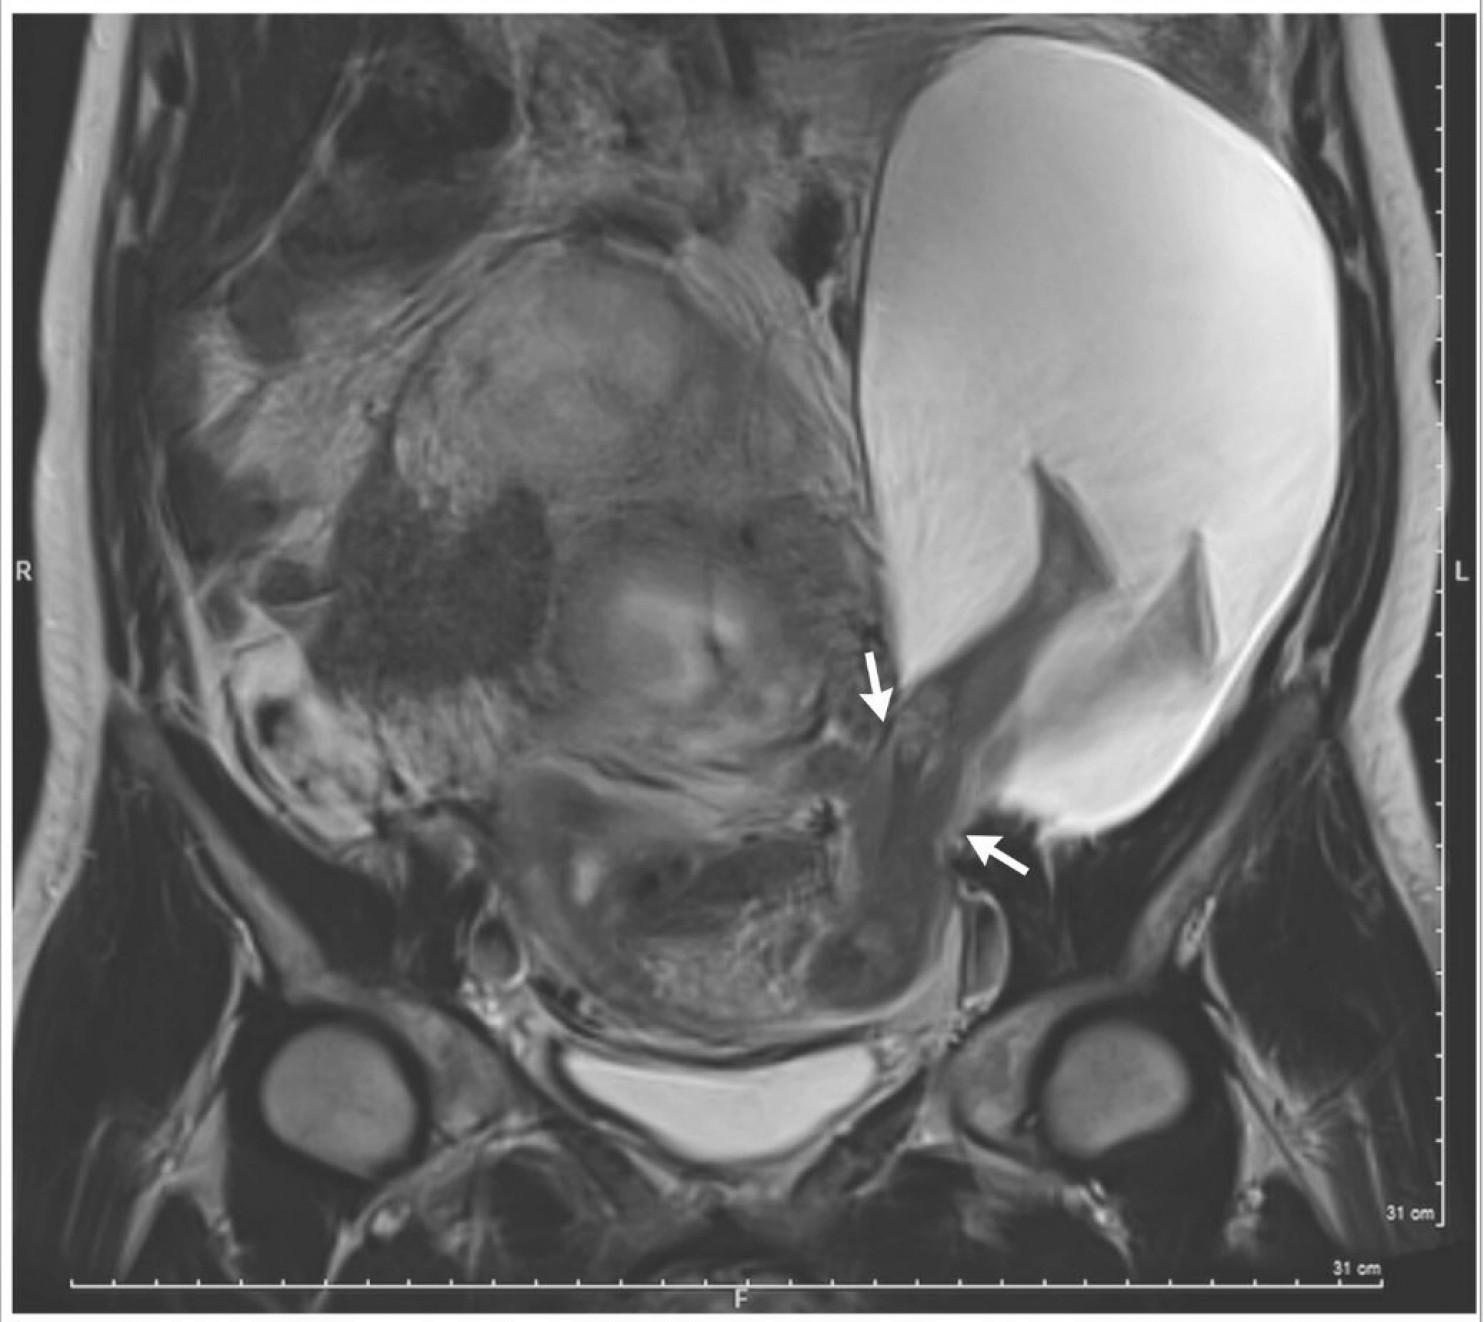

Sur les scanners, on l’aperçoit : une paire de jambes qui dépasse de l’utérus. Le cas est très rare, et tout autant impressionnant. Le New England Journal of Medine se fait l’écho de cette grossesse peu ordinaire, prise en charge au CHU d’Angers et commentée par le médecin dans les colonnes du Washington Post.

Au gré de la grossesse, cette rigidité a provoqué une déchirure de la paroi utérine, désignée sur l’IRM par des flèches. Le cas est très rare, c’est le 27e de l’histoire de la gynécologie obstétrique. Autre fait inhabituel : la patiente est restée asymptomatique, alors que les femmes qui subissent des ruptures utérines ressentent des douleurs intenses en raison de saignements internes. Mais « la hernie ombilicale a comprimé les bords de la déchirure utérine, et a eu un effet hémostatique » précise encore le médecin. En plus de cela, les jambes du fœtus ont « bouché » la déchirure, ce qui explique qu’il n’y ait pas eu de pertes sanguines. Le bébé, né par césarienne et prématuré, se porte aujourd’hui très bien.

(The New England Journal of Medicine)Effet "bouchon"